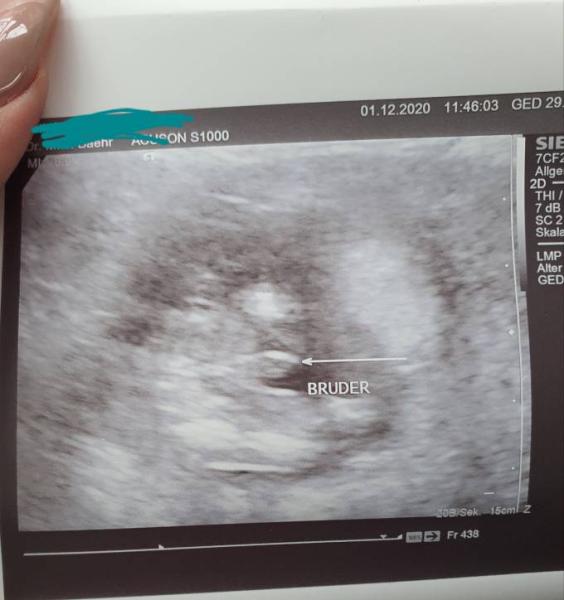

Also unser Outing für einen Jungen sah am Montag bei 17+5 so aus:

Bild zu